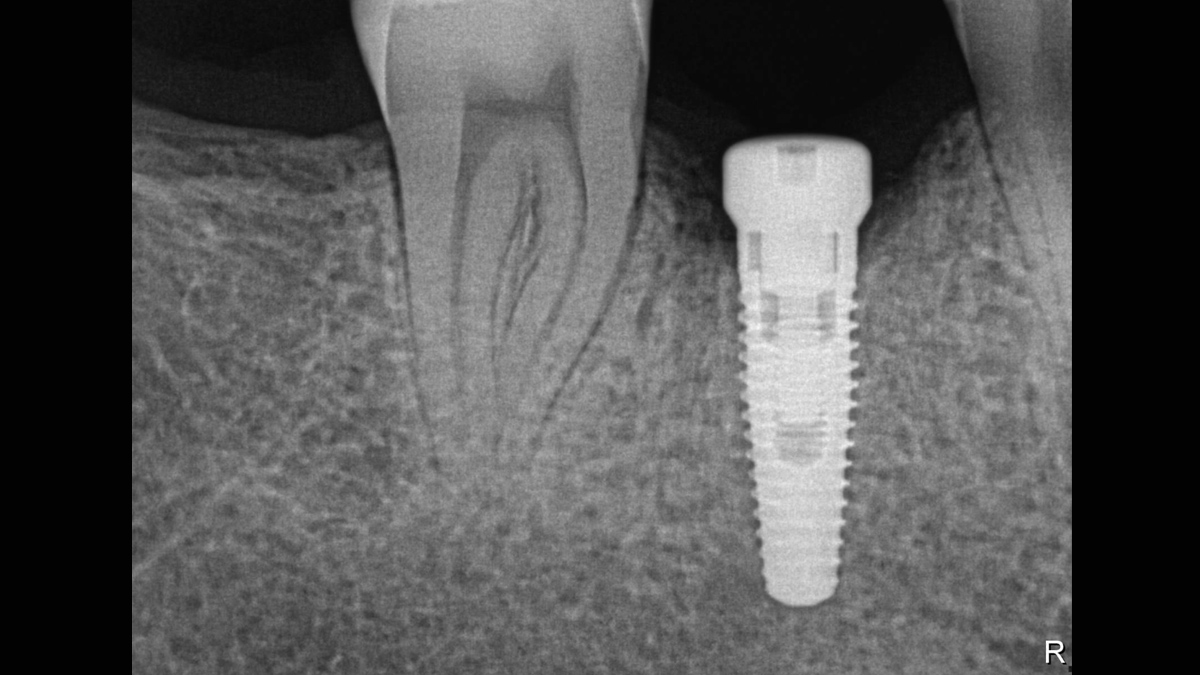

Excellent Image Quality

Xios XG Supreme provides a theoretical resolution of 33 lp/mm and a 15 μm pixel size.

Gallery of Sample Images